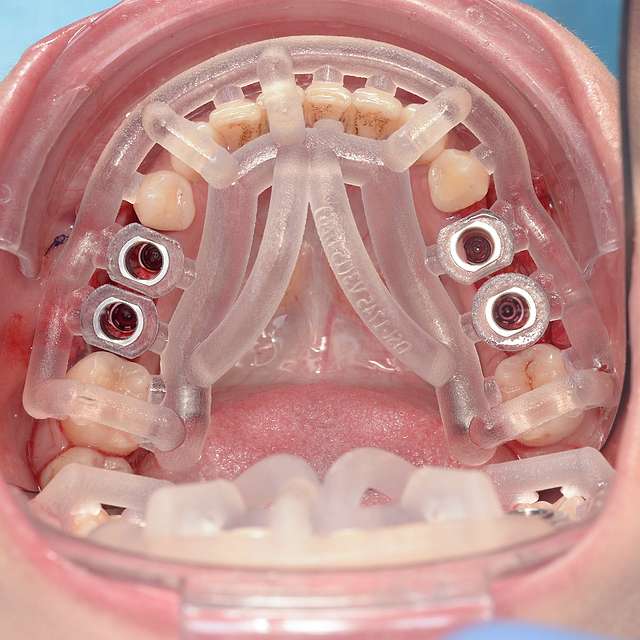

Surgical guides are used for more safety and precision in complex cases that require dental implant therapy. Guides are 3D printed based on the digital planning of the surgery, using specialised software and the CBCT of the patient.

For optimal esthetic results, the final design must always be the refference for the surgery. This design together with the CBCT of the patient are compiled to find the ideal position of the dental implants.

Guided surgery is safe and precise. A surgical guide is recommended in difficult or complex cases, to minimise risks and complications.